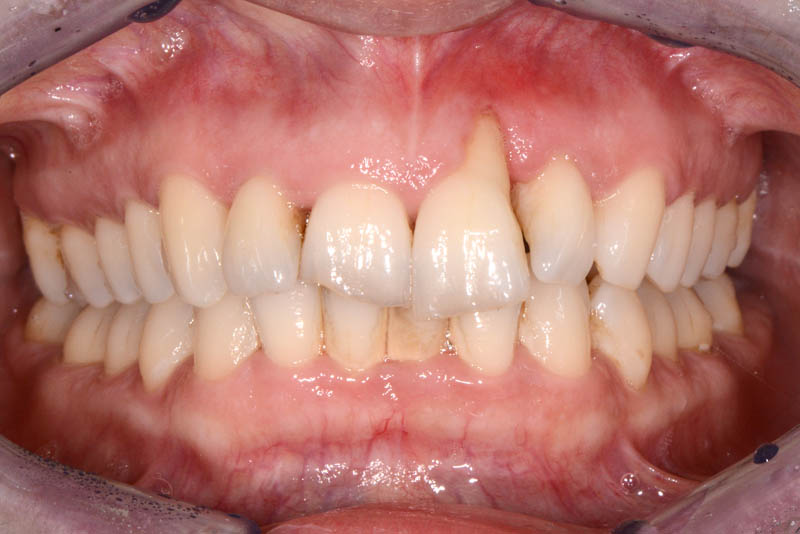

The rehabilitation of this periodontally compromised tooth required a multidisciplinary approach, combining both periodontal and orthodontic treatments.

Following an initial phase of non-surgical periodontal therapy aimed at removing subgingival calculus, Dr. Anna Mariniello performed both upper and lower alignment using a lingual, non-bracket orthodontic technique, employing active retainers applied to the lingual surfaces of the teeth.

The healing has now reached a 5-year follow-up.

5 years Follow up